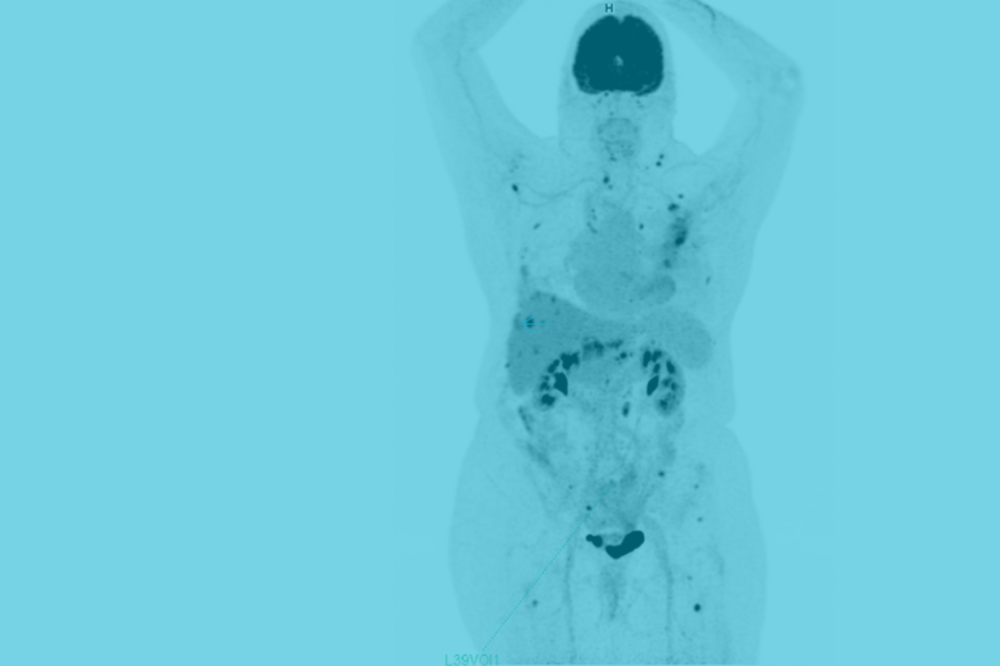

Le centre privé de recherche et développement (R&D) Euranova, spécialisé dans la science des données et l’IA, et l’Institut Carnot CALYM annoncent une collaboration avec le soutien institutionnel de Roche pour faire avancer la recherche clinique en imagerie médicale, qui se concentrera sur le lymphome folliculaire.